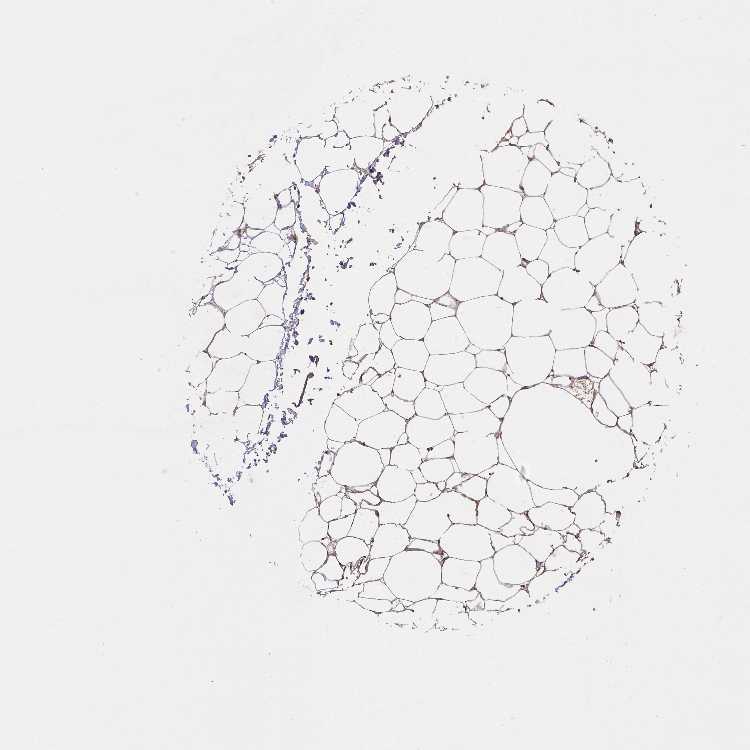

ADIPOSE TISSUE - Antibody stainingi

Antibody staining in the annotated cell types in the current human tissue is reported as not detected, low, medium, or high, based on conventional immunohistochemistry profiling in selected tissues. This score is based on the combination of the staining intensity and fraction of stained cells.

Each image is clickable and will lead to virtual microscopy that enables deeper exploration of all samples and also displays staining intensity scores, fraction scores and subcellular localization as well as patient and tissue information for each sample.

Antibody HPA061318

Adipocytes Not detected